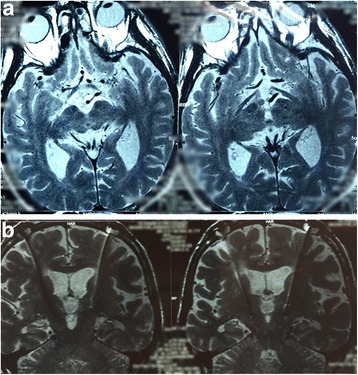

We located the subthalamic nucleus by preoperative magnetic resonance imaging (MRI 3.0 T) with Leksell stereotactic frame, then compute accurate coordinates of the target by surgical-plan system, the subthalamic nuclei dorsolateral part was selected as the target; intraoperative microelectrode localization was taken use of the electrophysiological recordings, then we made a stimulation test to observe the reaction of patients to different voltages after electrode implantation, an impulse generator (IPG) was implanted subcutaneously when patients were under general anesthesia. All patients underwent MRI (1.5 T) postoperatively for the assessment of target location and surgical complications (Fig. 1). Patients followed the doctor’s advices to continue to take medicine and without stimulation settings temporarily.

Fig. 1.

a. The lead location by the axial view of postoperative MRI. b. The lead location by the coronal view of postoperative MRI